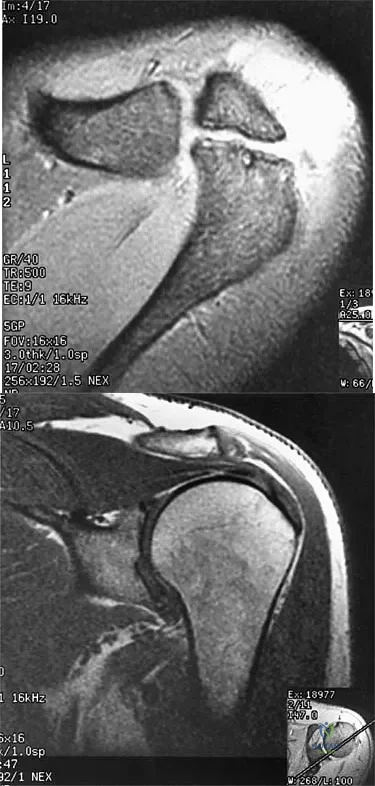

A 47-year-old male tennis player has pain in his nondominant shoulder that has failed to respond to 4 months of nonsurgical management. Examination reveals acromial tenderness and pain at the supraspinatus tendon insertion. He has a positive impingement sign, pain on forward elevation, and minimal cuff weakness. The MRI scans are shown in Figures 30a and 30b. To completely resolve his symptoms, treatment should consist of